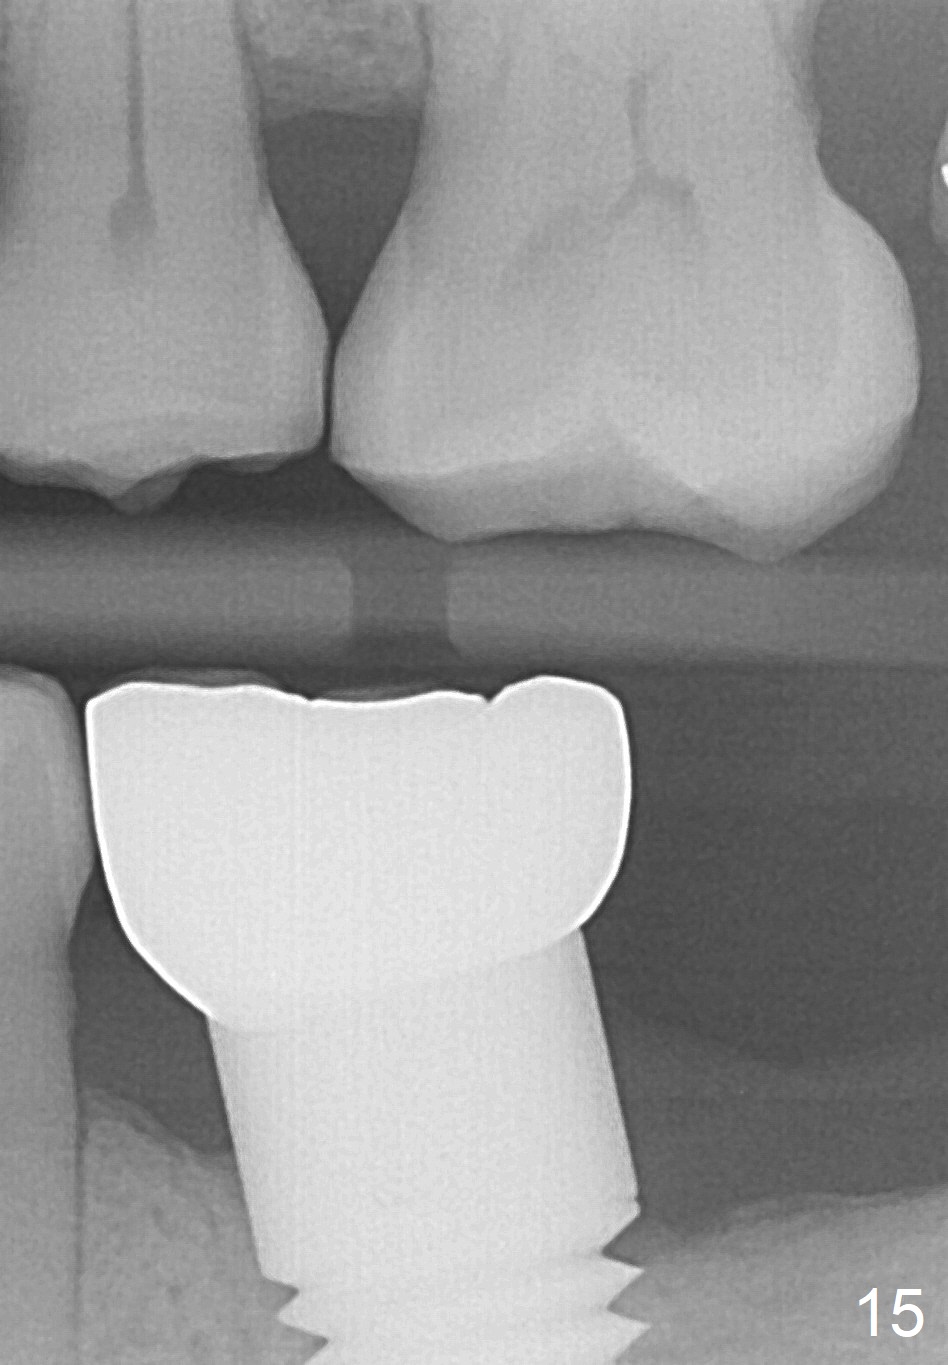

A 46-year-old female patient requests restoration of the lower left 1st molar (Fig.1). Although the patient refuses diabetes treatment, her wounds usually heal uneventfully. Her gag reflex is active. She could not tolerate a removable partial denture, which replaced the missing 2nd molar. Preop PA and CT shows extensive bone loss around the residual roots (Fig.1,2,4). It appears that extraction is simple. Immediate implant should not add too much additional trauma (Fig.3,5). Arrowheads in Fig.3,5 indicate the extent of osteotomy for implantation. With meticulous surgical manipulation, the wound should heal normally.

The patient returns for #19 restoration one year postop. The distal coronal threads appear not covered by bone (Fig.10 *) with distobuccal gingival recession (Fig.11). The buccal bulging (Fig.11 arrowheads) may be related to thin or no buccal plate. Bone graft at time of immediate implant may decrease the likelihood. In addition, the implant is placed buccally slightly (Fig.12). The gingival recession appears to have decreased 1 year 9 months post cementation (Fig.13). A thick keratinized gingiva forms around the implant at #8 1 year 11 months post cementation. There seems to be no bone loss 2.5 years post cementation (Fig.14,15, as compared to Fig.10)